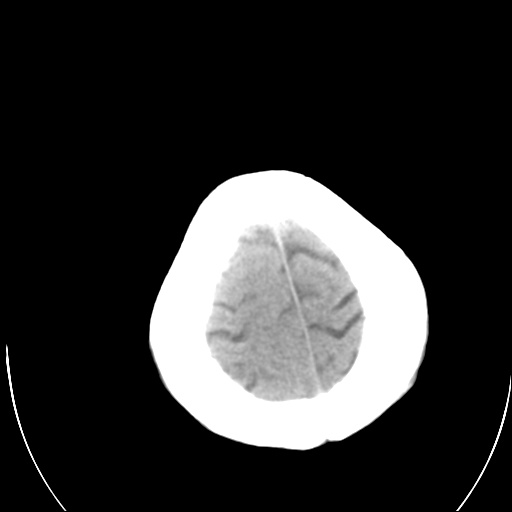

以下是引用泪洒红尘在2009-3-23 19:53:00的发言:[br]第四脑室以上脑室明显扩大,脑沟脑裂无明显增宽加深征象,符合交通性脑积水ct表现。

以下是引用xulianj在2009-3-23 20:31:00的发言:[br]右侧侧脑室扩大,中线结构左移,考虑梗阻性脑积水,建议mri检查。